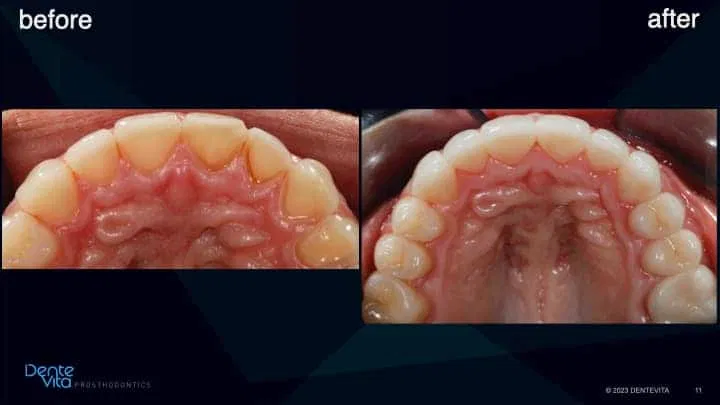

Teeth wear/erosion results in missing tooth structure. When this occurs, teeth naturally vertical/horizontally drift in order for the teeth to re-establish contact with the opposing or adjacent teeth, thereby enabling us to chew food effectively. However, if we would like to establish correct tooth length/dimensions once again, this is challenging to perform, especially in a conservative manner, since restorative space is lost.

One option to reverse tooth drift is by utilizing pre-orthodontic treatment solutions to intrude/translate affected teeth, thereby re-establishing correct tooth position, gum-line positions, and re-capture vertical/horizontal restorative space for future teeth rehabilitation/restoration.

This case study addressed significant tooth erosion from gastric reflux. Lost vertical space from vertical tooth drift was reversed with orthodontic treatment (intrusion and alignment therapy).